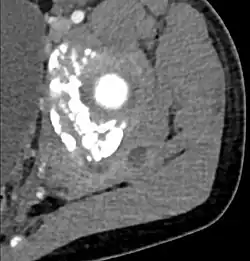

CT exam showing a multiloculated fluid collection in the left gluteus minimus muscle found to be a staph aureus pyomyositis in a 12-year-old healthy boy.

| Diagnostic method | Diagnostic method used for PM includes ultrasound, CT scan and MRI. Ultrasound can be helpful in showing muscular heterogeneity or a purulent collection but it is not useful during the first stage of the disease. CT scan can confirm the diagnosis before abscesses occur with enlargement of the involved muscles and hypodensity when abscess is present, terogenous attenuation and fluid collection with rim enhancement can be found. MRI is useful to assess PM and determine its localization and extension |